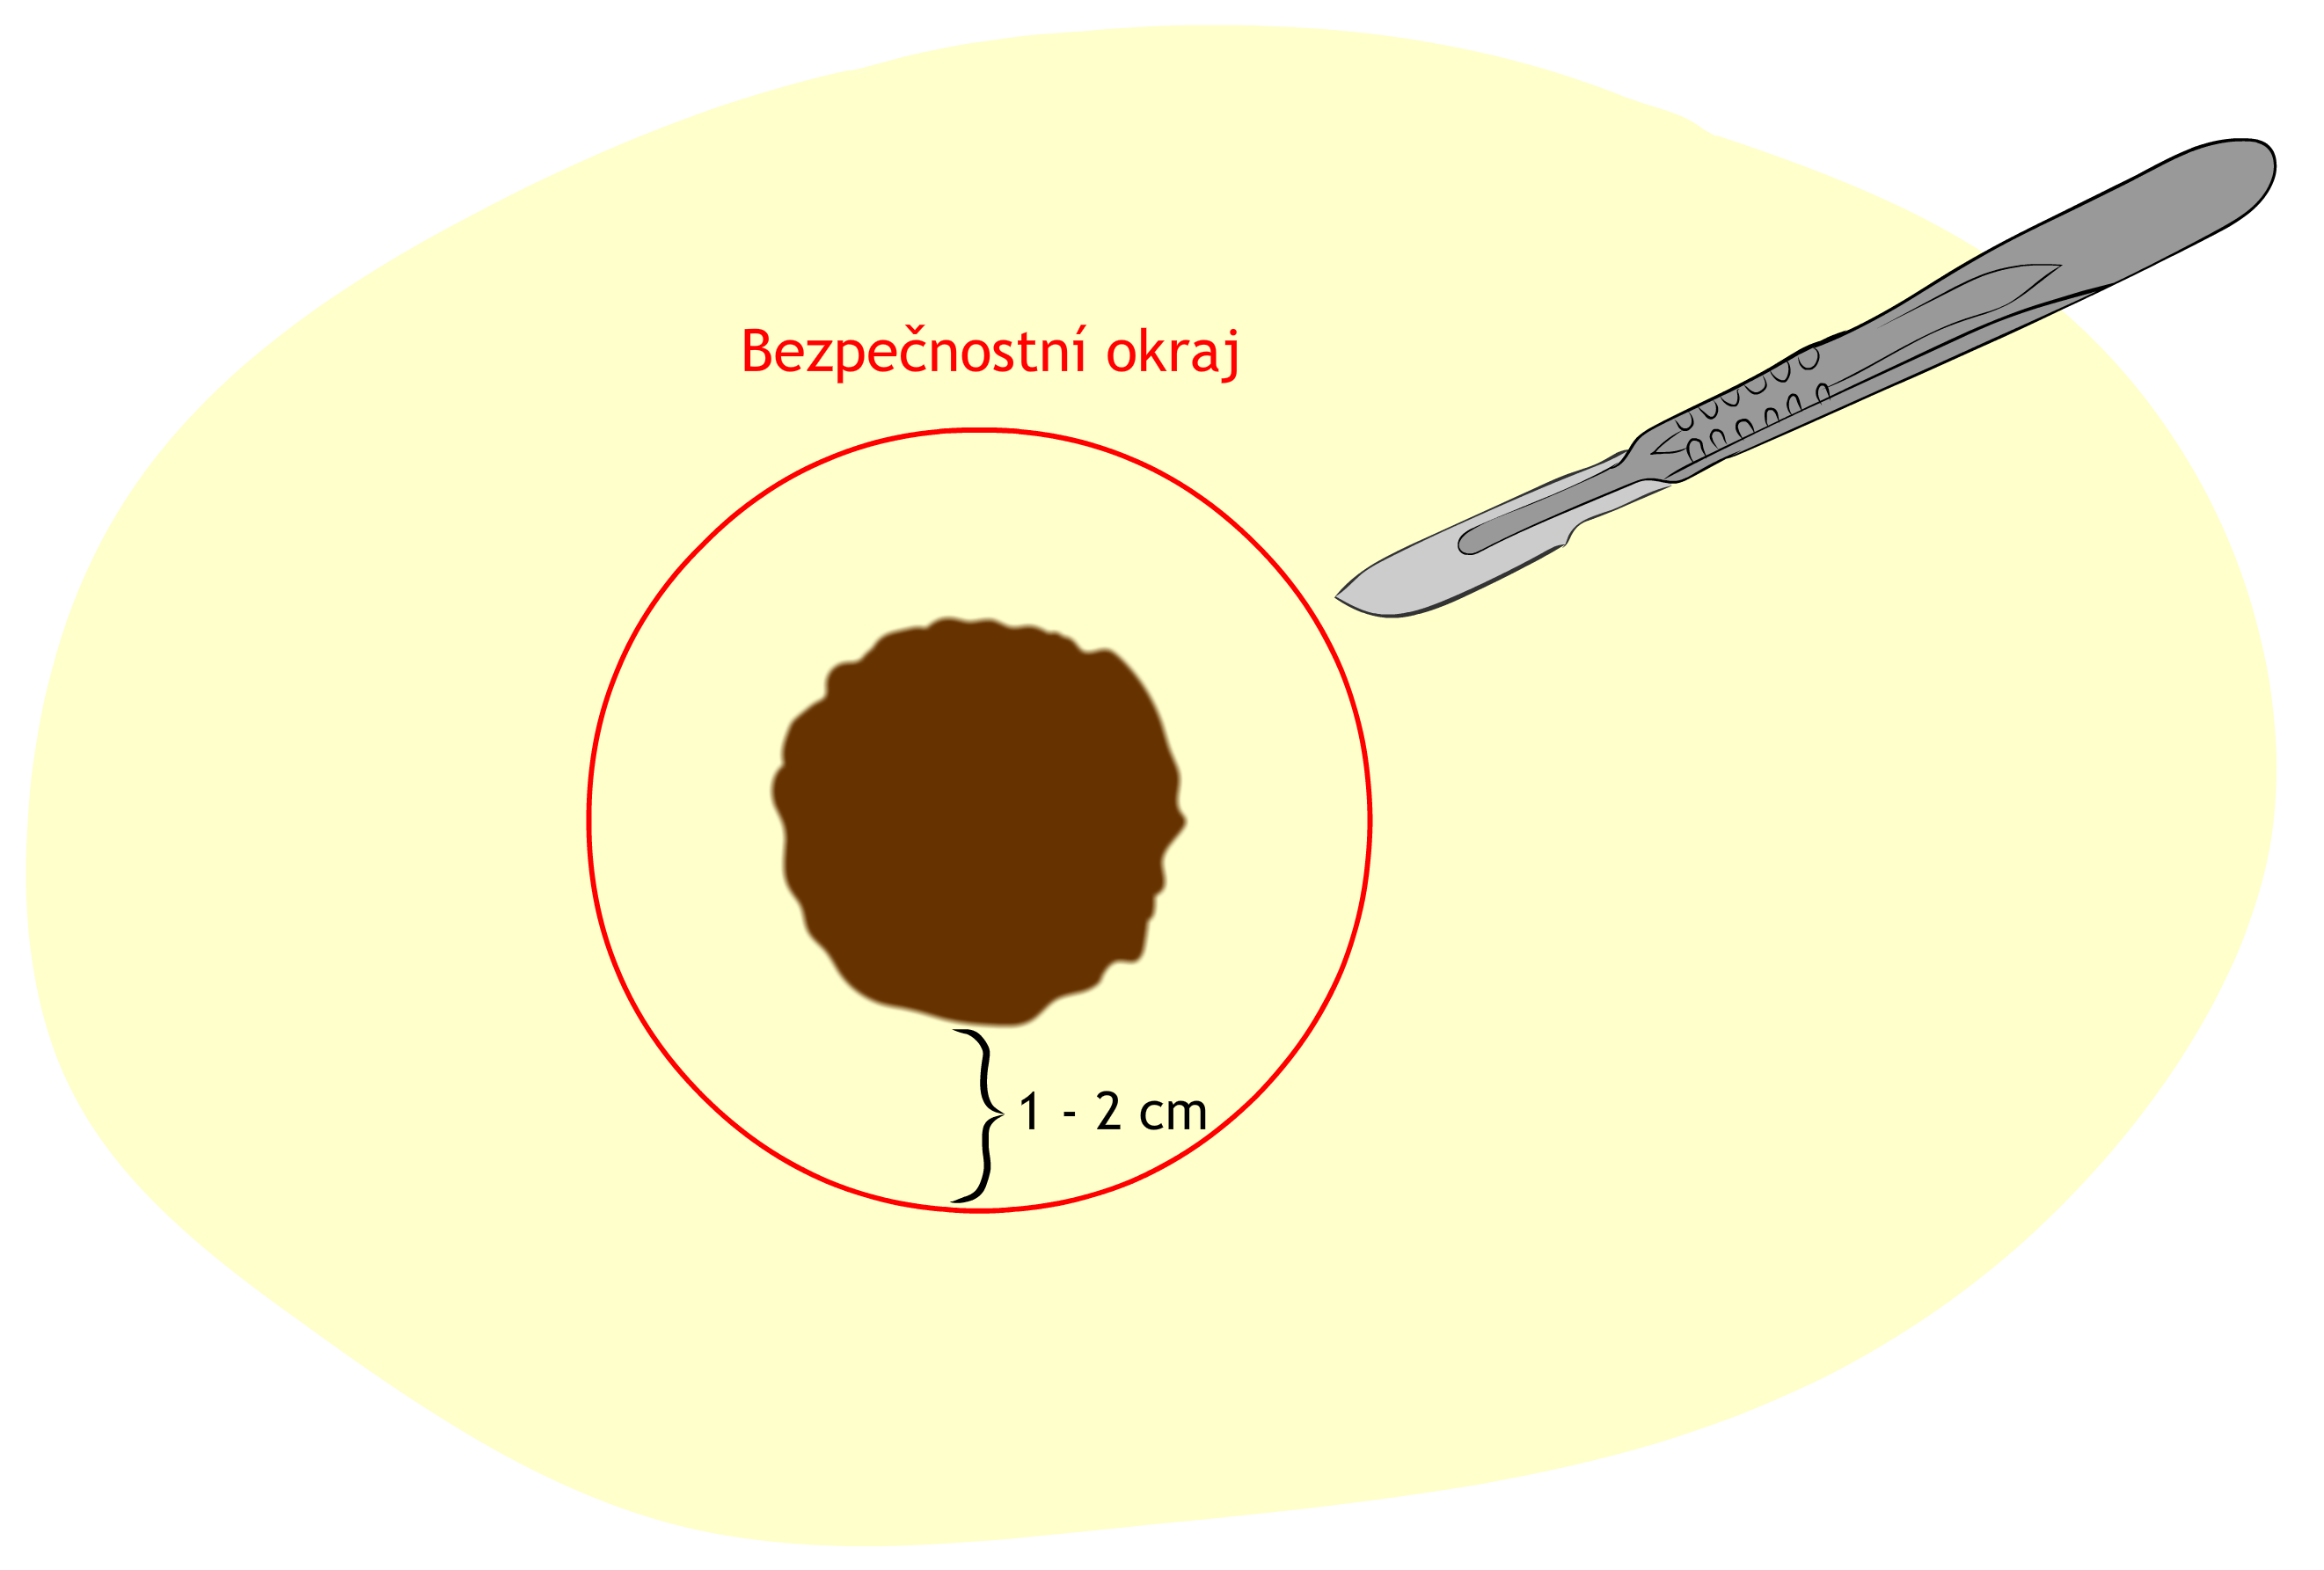

Základem je chirurgické odstranění melanomu – čím dříve, tím lépe. Na základě jeho hloubky invaze do kůže (Breslowův index) je spolu s tumorem odstraněn i patřičně široký lem zdravé tkáně okolo tumoru - většinou se jedná o 1-2 cm široký bezpečnostní lem.

Takto po vyříznutí tumoru vzniká relativně rozsáhlý defekt, který je v některých případech nutné zakrýt kožním štěpem nebo lalokovými plastikami (podrobnější informace o uzavírání defektů po tumorech jsou k dispozici ZDE)